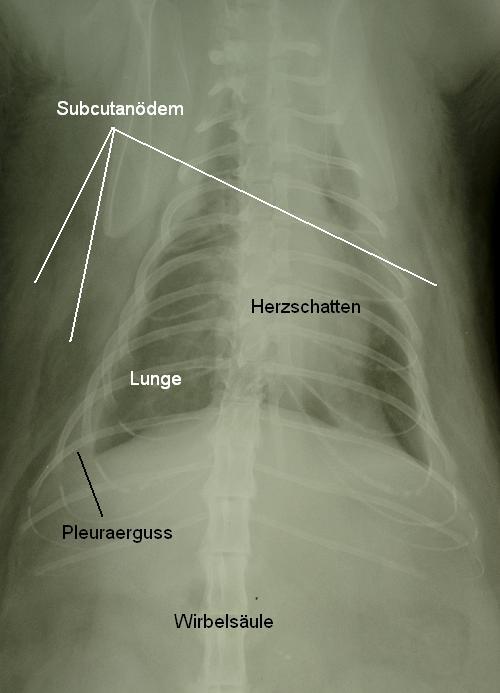

Die Röntgenaufnahmen zeigen einerseits einen Pleuraerguss (abnormale Ansammlung von Flüssigkeit in der Brusthöhle) sowie ein Lungenödem und scheinen verdächtig für einen Aszites (abnormale Ansammlung von Flüssigkeit in der Bauchhöhle). Die Herzsilhouette ist aufgrund des Brusthöhlenergusses kaum abgrenzbar.